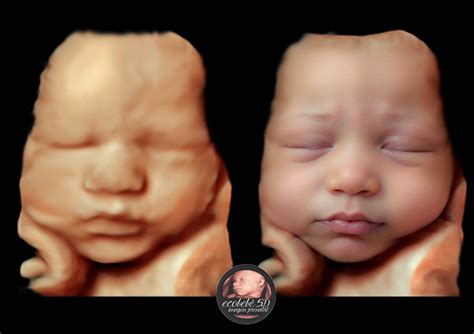

Ecografía 4D y 5D: Experiencias Inmersivas

Centros como Centre Miramed ofrecen tecnologías avanzadas como la ecografía 4D y 5D, que van más allá de la visualización médica para crear experiencias emocionales. La tecnología Hiper-Realismo Motion permite que el rostro del bebé cobre vida en secuencias de vídeo cortas, ofreciendo una vivencia aún más emocionante.

Centre Miramed, con sedes en Granollers y Sant Cugat, se posiciona como un centro de referencia en la provincia de Barcelona, ofreciendo ecografías 5D cerca de Terrassa, Cerdanyola, Mollet del Vallés, Rubí, Santa Perpetua, Sabadell, Mataró y Vic.